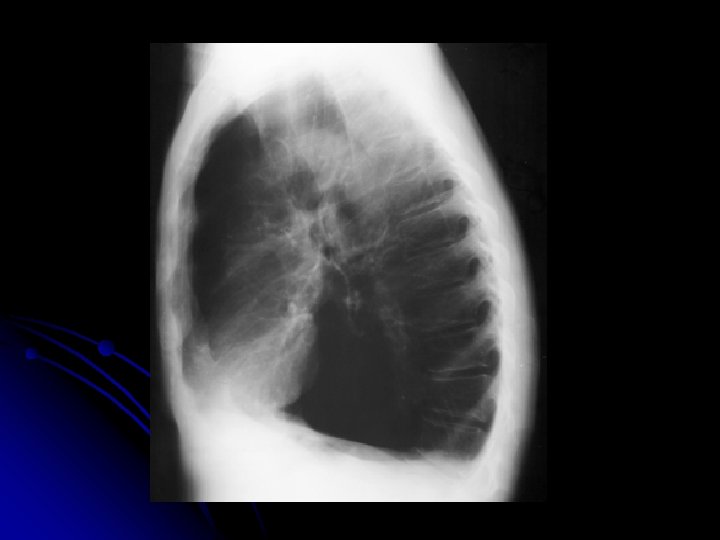

MS 76 yaşında, erkek hasta İş adamı

YAKINMASI Nefes darlığı (eforla) l Öksürük l Balgam çıkarma (mukoit) l Halsizlik l

Özgeçmiş l Kot kırıkları 4 yıl önce, travma öyküsü yok

ALIŞKANLIKLARI 50 paket/yıl sigara 10 yıldır bırakmış

FİZİK MUAYENE l l l Genel durum iyi, bilinç açık Dispne (+) Ateş: 36. 8 ‘C TA: 150/90 mm. Hg Nabız 100/dk, ritmik Kalp sesleri: S 1, S 2 doğal. S 3(-)

Solunum Sistemi l DSS: 30/dk, l l l torakoabdominal. Bilateral solunum sesleri azalmış. Ekspiryum uzun Tek tük wheezing mevcut

Fizik Muayene Dispneik Ödem Karaciğer kot kenarını geçiyor

SFT FVC: 1740 ml(%59) FEV 1: 640 ml(%29) FEV 1/FVC: %37 FEF 25 -75: 0, 22(%9)

VOLÜMLER Pletismografik TLC: 7240 ml(%136) RV: 3780 ml(%140) RV/TLC: %52

DİFÜZYON KAPASİTESİ DLCO m. L/mm. Hg/dak l DLCO/VA m. L/mm. Hg/dak /L l %26 %32

AKG Pa. O 2: 47. 2 mm. Hg Pa. CO 2: 39 mm. Hg Sa. O 2: %85 p. H: 7. 4 HCO 3: 28. 4

Hasta GOLD a göre hangi evrededir? l l HAFİF ORTA AĞIR ÇOK AĞIR